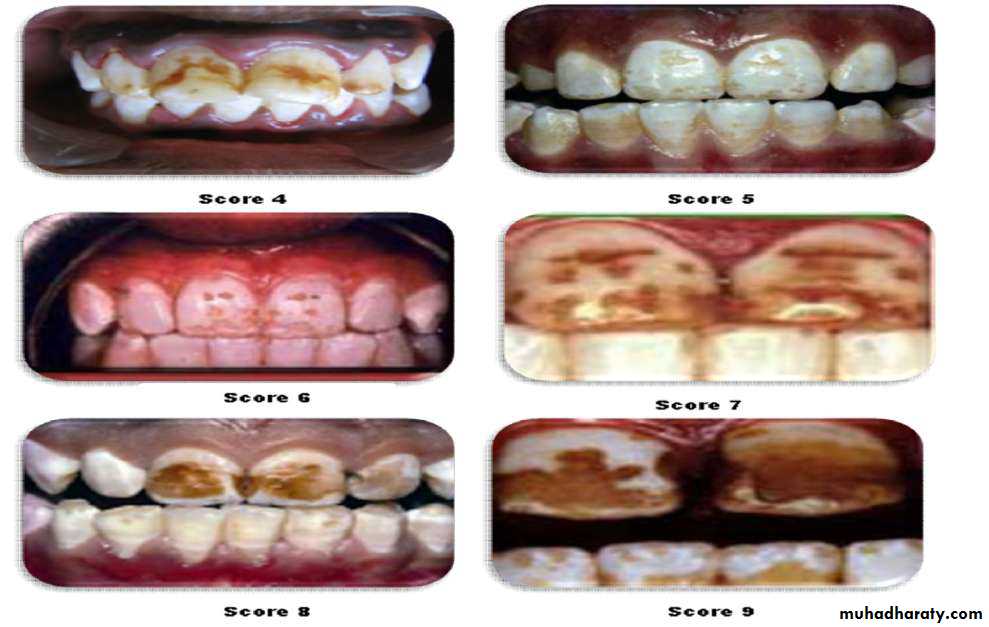

Thylstrup and Fejerskov Index for Fluorosis

1978TFI given By Thylstrup A. and Fejerskov O.

Purpose-to refine modify and extend the Dean’s Index.

10 point classification system designed to characterize the macroscopic appearance of teeth in relation to the

underlying histological condition of enamel.

In 1988 TFI was modified by Fejerskov - 0nly one surface examined

It is possible to produce exact and comparable estimates of severity of dental fluorosis in various populations by

1. Frequency distribution of TF score of individual teeth.

2. Cumulative distribution of severity of the TF scores.

• It attempts to validate the visual appearance against the histological defect.• Most sensitive of all fluorosis measuring indices.

• Granath et al. (1985), comparing the DEAN and T-F indexes, concluded that the latter was more detailed and sensitive because it was based on biological aspects where there is an increase in hypo mineralization with a simultaneous increase in the depth of the enamel surface in direction of the amelo-dentin junction.

They concluded that the T-F index is the most indicated for work where detailed information about the problem is required.